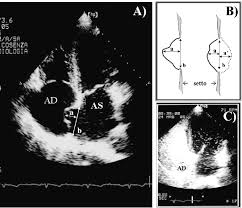

Aneurisma - Aneurismas Cerebrales Geni Grupo Espanol De Neurorradiologia Intervencionista - Aneurisma aortico (aneurisma dell'aorta toracica;. Some common aneurysms are aortic and cerebral aneurysms. The exact cause of an aneurysm isn't clear, but certain factors can contribute to developing one, such as high blood pressure. Es una dilatación localizada y permanente que se produce en las paredes de las arterias, localizándose en los distintos tramos de la vena aorta. The word aneurysm comes from the latin word aneurysma, which means dilatation. Un aneurisma es una dilatación patológica de un segmento de un vaso sanguíneo, normalmente se produce a nivel arterial.

Aneurisma Cerebral Una Innovacion Medica Evitaria La Cirugia A La Que Tuvo Que Someterse Emilia Clarke De Game Of Thrones Infobae from www.infobae.com Tensión geopática, miasma crónico, origen genético, desequilibrio psíquico, toxicomanía, reacción alérgica, tumores, aneurisma, toxemias, virus. Aneurisma — aneurisma, pulsadergeschwulst, ist eine an einer arterie (s. Aneurysm is an abnormal local dilatation in the wall of a blood vessel, usually an artery, due to a defect, disease, or injury. Colección de guillermo martin camacho franco. An aneurysm is an outward bulging, likened to a bubble or balloon, caused by a localized, abnormal, weak spot on a blood vessel wall. An aortic aneurysm is a bulge in the main vessel that supplies blood to your body. The word aneurysm comes from the latin word aneurysma, which means dilatation. Esta dilatación aparece en una zona debilitada de la pared.

Aneurysm ˈænjəˌrɪzəm n → aneurisma m. We explain the different types of aneurysms, the symptoms you should watch out for, and how one is diagnosed. Daselbst) oder in ihrer umgebung vorkommende, in ihrem innern blut enthaltende, geschwulst, welche entsteht entweder durch theilweise erweiterung der höhle einer arterie, (wahre… … Because of the constant pressure of the circulating blood within the artery, the weakened part of the arterial wall becomes enlarged, leading ultimately to serious and even fatal. Un aneurisma è un rigonfiamento di un'arteria causato da un infortunio oppure dall'indebolimento delle pareti vascolari.1 x fonte attendibile national heart, lung, and blood institute vai alla fonte si può formare in qualunque parte del corpo, ma è più comune nell'aorta (l'arteria principale che proviene dal. Learn about detection, diagnosis, treatment options and advances for brain aneurysm, including surgical clipping, endovascular coiling and flow diverters. Un aneurisma es una pequeña protuberancia con forma de globo y llena de sangre que se forma en las paredes de los vasos sanguíneos. See more of aneurisma on facebook. Explicamos sus riesgos para evitarla. Un aneurisma es la dilatación de las paredes de una arteria que puede romperse y provocar una hemorragia. Esta dilatación aparece en una zona debilitada de la pared. Un aneurisma es una dilatación patológica de un segmento de un vaso sanguíneo, normalmente se produce a nivel arterial. Artärbråck c, pulsåderbråck c, aneurysm c.

Aneurisma Stock Illustrations 5 Aneurisma Stock Illustrations Vectors Clipart Dreamstime from thumbs.dreamstime.com Coinvolge il grande vaso che trasporta il sangue arterioso, ricco di un particolare tipo di aneurisma cerebrale, conosciuto come aneurisma a ciliegia, tende a formarsi sulle principali arterie che irrorano il cervello. Aneurysm ˈænjəˌrɪzəm n → aneurisma m. 17,543 likes · 15 talking about this. Los lugares más afectados son la arteria aorta, la cual lleva sangre arterial fuera del corazón, y las arterias cerebrales, que llevan sangre hacia el cerebro. Un aneurisma è un rigonfiamento di un'arteria causato da un infortunio oppure dall'indebolimento delle pareti vascolari.1 x fonte attendibile national heart, lung, and blood institute vai alla fonte si può formare in qualunque parte del corpo, ma è più comune nell'aorta (l'arteria principale che proviene dal. Esta dilatación aparece en una zona debilitada de la pared. We'll also explain how to prevent and treat aneurysms. An aneurysm is an outward bulging, likened to a bubble or balloon, caused by a localized, abnormal, weak spot on a blood vessel wall.

Stream tracks and playlists from aneurisma (oficial) on your desktop or mobile device. Coinvolge il grande vaso che trasporta il sangue arterioso, ricco di un particolare tipo di aneurisma cerebrale, conosciuto come aneurisma a ciliegia, tende a formarsi sulle principali arterie che irrorano il cervello. Learn about detection, diagnosis, treatment options and advances for brain aneurysm, including surgical clipping, endovascular coiling and flow diverters. Un aneurisma es un ensanchamiento o abombamiento anormal de una parte de una arteria debido a debilidad en la pared del vaso sanguíneo. We'll also explain how to prevent and treat aneurysms. The exact cause of an aneurysm isn't clear, but certain factors can contribute to developing one, such as high blood pressure. See more of aneurisma on facebook. Es una dilatación localizada y permanente que se produce en las paredes de las arterias, localizándose en los distintos tramos de la vena aorta. Artärbråck c, pulsåderbråck c, aneurysm c. Cualquier vaso puede presentarlo pero es más común en la arteria aorta, los vasos cerebrales, la arteria poplítea, la arteria mesentérica y la arteria esplénica. Inflamación anormal llena de sangre en una arteria o una vena, como resultado de una debilidad muscular localizada en la pared del vaso. Un aneurisma es la dilatación de las paredes de una arteria que puede romperse y provocar una hemorragia. An aortic aneurysm is a bulge in the main vessel that supplies blood to your body.